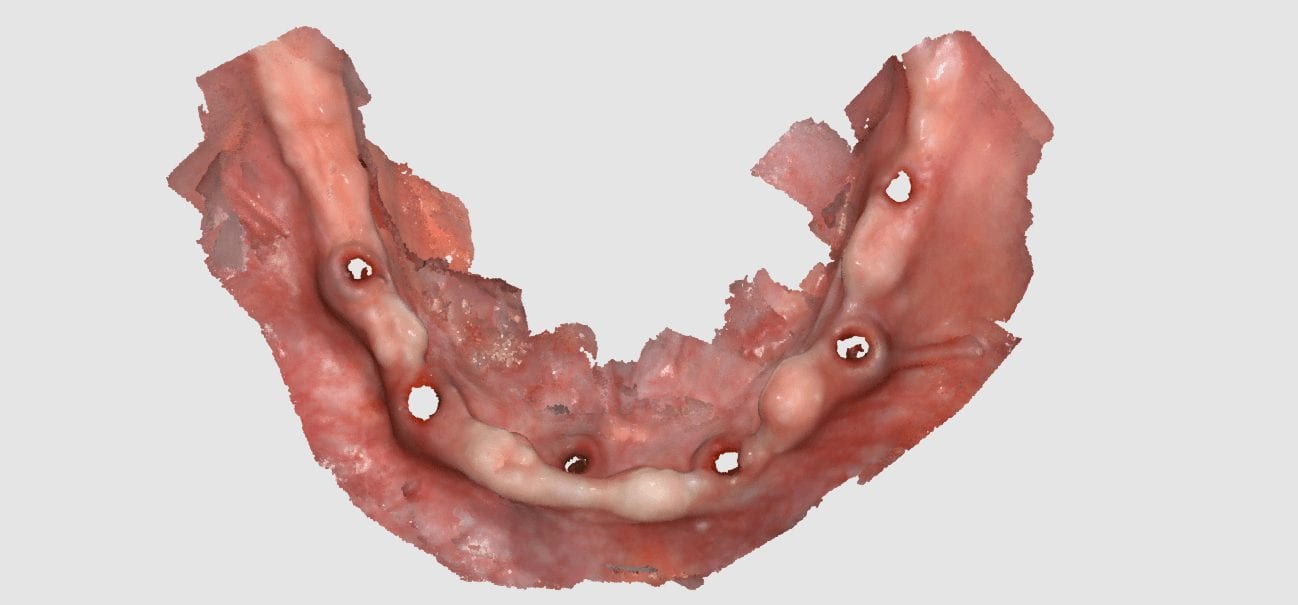

June 25, 2019This case shows the amount of control one can have over the fit of a restoration. The upper right first molar was imaged with the Medit i500 and then imported […]